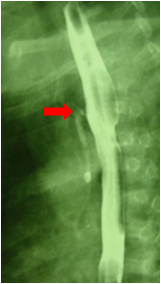

2.颈、胸、腹正侧位X线摄片示导管卷曲或造影显示食道近端盲袋。